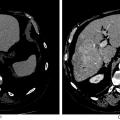

Nodule hépatique

CARCINOME HEPATOCELLULAIRE